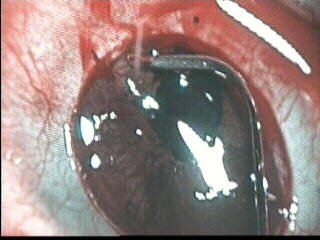

www.journeyman.tv/?lid=10140 Taiwan - New Eyes - 7 min 12 sec [18 October 2001]